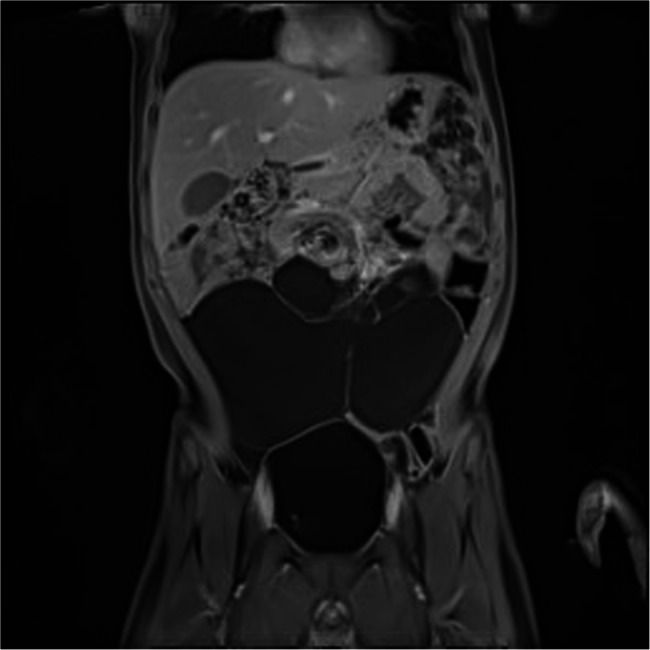

Laparoscopic management of giant abdominal cystic lymphangiomas: experience from the queen Fabiola children's university hospital.